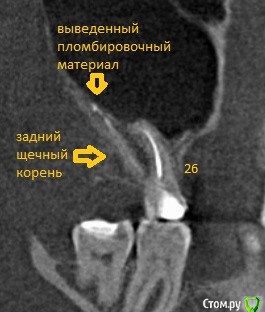

alex-forever Опубликовано 10 июля, 2017 Поделиться Опубликовано 10 июля, 2017 Добрый день, пролечили зуб, вышел пломбировочный материал за пределы корня. С момента лечения прошло две недели, КТ сделали в прошлый четверг. Цитата из заключения: Просвет канала заднего щечного корня прослеживается на всем протяжении, заполнен пломбировочным материалом. Определяется выведение пломбировочного материала в структуру стенки левого верхнечелюстного синуса. В мезиобуккальном корне МВ1 и МВ2, просветы их прослеживаются, запломбированы. Небный корень так же запломбирован до апикального отверстия. Пульпарная камера заполнена пломбировочным материалом. КТ: Подскажите, может ли возникнуть перфорация, нагноение и т.п.? Проще всего гайморит, синусит и прочее? Ссылка на комментарий

St. Опубликовано 10 июля, 2017 Поделиться Опубликовано 10 июля, 2017 Нет, все с Вашим зубом по КТ хорошо. Выведение материала в таком колличестве считается в пределах нормы и на прогноз никак не влияет. 2 Ссылка на комментарий

alex-forever Опубликовано 10 июля, 2017 Автор Поделиться Опубликовано 10 июля, 2017 Нет, все с Вашим зубом по КТ хорошо. Выведение материала в таком колличестве считается в пределах нормы и на прогноз никак не влияет.А то что материал практически с пазухой контактирует ничего страшного? Ссылка на комментарий

St. Опубликовано 11 июля, 2017 Поделиться Опубликовано 11 июля, 2017 Ничего страшного, современные материалы нейтральны и не раздражают окружающие ткани. Не переживайте! Ссылка на комментарий